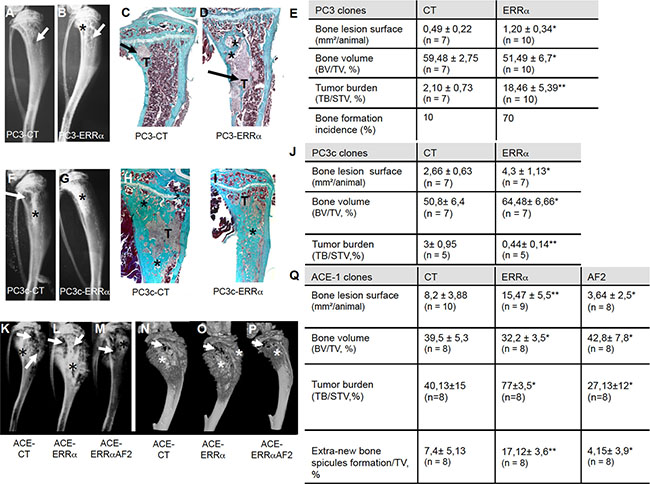

ERRα in PCa cells promotes tumor cells progression in vivo in bone microenvironment

To address ERRα function in PCa bone progression, we used three CRPC pre-clinical models, two human models (PC3 and PC3c) and one canine model (ACE-1). Specifically, a full-length ERRα cDNA was stably transfected into PC3 cells, which are known for their capacity to form osteolytic lesions in vivo [27]. Three independent PC3-ERRα clones (overexpressing ERRα) and three PC3-CT clones (harboring empty vector) were generated (Figure 1E, 1F). In parallel, to validate further the human PC3 model, human PC3c and canine ACE-1 PCa cells that both induce mixed bone lesions (with both osteolysis and osteoformation) were stably transfected with full-length ERRα cDNA (Figure 1H, 1J) [28] [29]. ACE-1 cells were also transfected with cDNA containing a truncated form of ERRα lacking the co-activator binding domain AF2 (AF2) (Figure 1J) [22]. Western blotting confirmed higher ERRα expression in PC3-ERRα, PC3c-ERRα and ACE-1-ERRα than in their respective control cells (Figure 1E, 1H, 1J). The presence of a slightly lower molecular weight band in AF2 in ACE-1 cells expressing the ERRα-AF2 deletion mutant corresponded well with its expected smaller size (AF2; Figure 1J) [22]. As expected, expression of mRNA for VEGF-A, a known ERRα target gene [30] was higher in all of the ERRα overexpressing clones (ERRα; PC3, PC3c and ACE-1) but not in the AF2 ACE-1 clone, confirming the increased activity and the dominant negative functions of both wild-type ERRα and the truncated ERRα-AF2 constructs respectively (Figure 1G, 1I, 1K). To assess whether and how levels of ERRα in tumor cells affected progression of bone lesions, PC3, PC3c and ACE-1 clones were inoculated via intra-tibial injections into SCID male mice (Figure 2). Three weeks (for PC3 (pool of the 3 clones for CT and ERRα respectively) and ACE-1 clones) (Figure 2 (PC3 (A–E), ACE-1 (K–Q)) and six weeks (for PC3c clones) (Figure 2 PC3c (F–J)) after tumor cell injections, radiographs revealed that animals bearing ERRα overexpressing tumors had increased bone lesion surfaces whereas ACE-AF2 tumors had decreased bone lesion surface compared to CT tumors (Figure 2 -PC3 (A–B), (Mann-Whitney, P = 0.011) (bone lesion surface mm2)(E), -PC3c (F-G), (Mann-Whitney, P = 0.0175)(J) -ACE-1 (K–M) (Mann-Whitney, P = 0.0079, P = 0.0304) (Q)). The stimulatory effect of ERRα on PCa-induced bone lesion surface was confirmed by three-dimensional micro-computed tomographic reconstruction (%BV/TV) (cortical and trabecular bone), with a decrease in bone volume in animals bearing PC3-ERRα and ACE-1-ERRα tumors (%BV/TV, Mann-Whitney, PC3 P = 0.022 and, ACE-1 P = 0.0411) suggesting an increase in bone destruction in both ERRα overexpression models (Figure 2E and 2Q, %BV/TV). The stimulatory effect of ERRα on PCa-induced bone lesion surface was also evident by histology (Figure 2 PC3(C,D)) and histomorphometric analysis (TB/STV) with an increase of skeletal tumor burden (Figure 2E and 2Q). Since the osteoblastic region is highly stimulated in the PC3c model (Figure 2H, 2I) (see the increased of the %BV/TV: (Mann-Whitney, P = 0.022)), the surface of the tumor (TB/STV) decreased in animals bearing PC3c-ERRα (Figure 2J (Mann-Whitney, P = 0.0023)) (asterisks showing bone formation). Similarly, 70% of mice bearing PC3-ERRα tumors exhibited small new bone formation compared to mice bearing PC3-CT tumors (Figure 2E). New bone formation was also seen in animals bearing ACE-1-ERRα versus ACE-1-CT tumors (Figure 2Q: extra-bone-new spicules surface formation/ tissue volume; Figure 2 (N-P) (asterisks mark extra-new spicules bone formation). The bone lesion surface and bone volume-new bone formation effects seen with ERRα overexpression were markedly abrogated in tumors bearing the dominant negative AF2-truncated ERRα (Figure 2K, 2M and 2N, 2P, 2Q). Taken together, our results indicate that overexpression of ERRα in PCa cells stimulates both new bone formation and destruction suggesting that it may be associated with mechanisms mediating mixed lesions in vivo.

Figure 2: Over-expression of ERRα in prostate cancer cells induced bone lesions development. Radiography revealed larger lesions in mice injected with (A, B) PC3-ERRα versus PC3-CT, and (F, G) with PC3c-ERRα versus PC3c-CT. Histology after Goldner’s trichrome staining confirmed the radiography results in mice injected with (C, D) PC3-ERRα versus PC3-CT (H, I) with PC3c-ERRα versus PC3c-CT (bone matrix in green). (E) Induction -of larger bone lesions surface in mice injected with PC3-ERRα (ERRα)(Mann-Whitney, P = 0.011), -of a decrease in %BV/TV (Mann-Whitney, P = 0.022) and an increase of %TB/STV (Mann-Whitney, P = 0.008) compared with mice injected with PC3-CT (CT). Bone formation incidence show that 70% of mice injected with PC3-ERRα (ERRα) developed some bone formation as opposed to 10% of mice injected with PC3-CT (CT). (J) Increased -of bone lesions surface in mice injected with PC3c-ERRα (Mann-Whitney, P = 0.0175), -of the %BV/TV (Mann-Whitney, P = 0.022) and decrease of the %TB/STV (Mann-Whitney, P = 0.0023) compared with mice injected with PC3c-CT (CT). Radiography (K–M) and 3D micro-tomography reconstructions (N–P) showed larger bone lesions in mice injected with ACE-ERRα versus ACE-CT with an abrogation of the bone lesion effects seen with ERRα overexpression in tumors bearing the dominant negative AF2-truncated ERRα. (Q) After 3 weeks post inoculation of ACE-ERRα, ACE-CT and ACE-AF2 cells, radiography revealed larger and smaller bone lesions surface in mice injected with ACE-ERRα and ACE-AF2 respectively compared to CT (Mann-Whitney, P = 0.0079, P = 0.0304) and microtomographic reconstructions of tibiae show a decrease in mice injected with ACE-ERRα compared to CT (%BV/TV: Mann-Whitney, P = 0.0411), an increase in %TB/STV (Wilcoxon, P = 0.034) compared to CT, and an increase in % new bone formation/TV (extra-bone spicules formation): (Mann-Whitney, P = 0.0025). The increase in bone lesion surface (Mann-Whitney, P = 0.0011), in the %TB/STV (Mann-Whitney, P = 0.0052), in the extra-bone spicules formation (Mann-Whitney, P = 0.0012) and the decrease in %BV/TV (Wilcoxon, P = 0.0273) effects seen with ERRα overexpression were markedly abrogated in tumors bearing the dominant negative AF2-truncated ERRα. * = P < 0.05; ** = P < 0.001; *** = P < 0.0001. T: Tumor; * bone formation; Arrow: bone degradation.